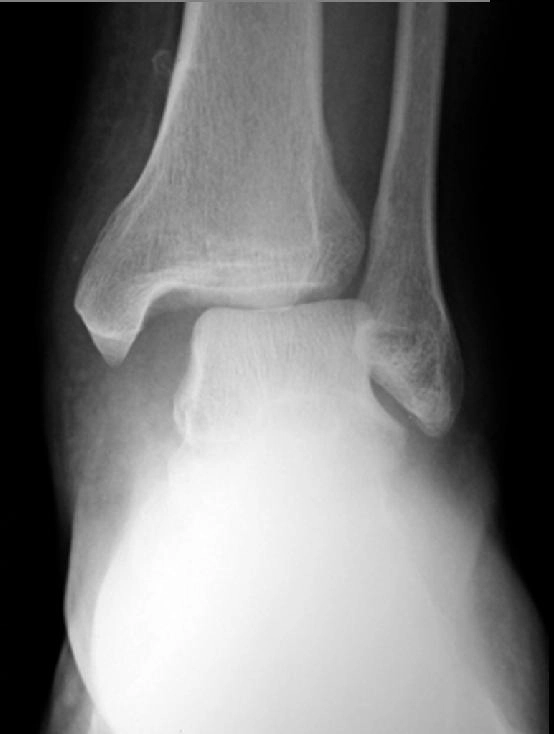

Gãy Maisonneuve (gãy đầu trên xương mác)

16/03/2026